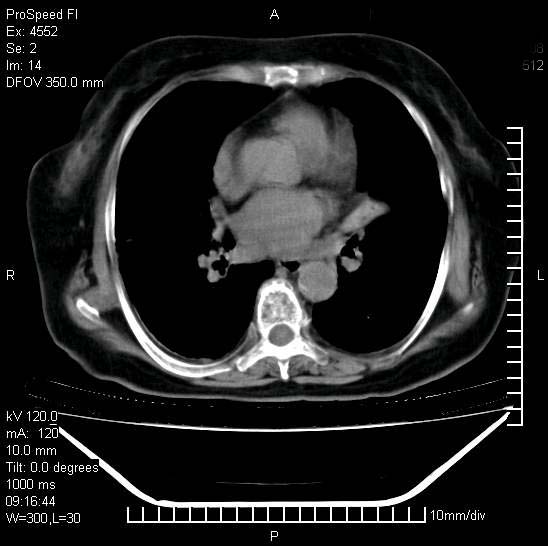

标题: CT15528:女性,79岁,近几日晚上高热,39度,仍咳少量血 [打印本页]

标题: CT15528:女性,79岁,近几日晚上高热,39度,仍咳少量血

十几年前曾患肺结核,一周前突咳血约100ml,中性粒细胞稍高,诊断两上肺陈旧结核,下肺炎症,给予抗炎治疗,近几日晚上高热,39度,仍咳少量血,4天前ct及今天ct上传。

[face=黑体]8月30日[/face]

支持陈旧性肺结核并两下肺感染,两侧胸腔积液。

短短几天内,病变范围明显增多扩大,以左侧明显,而且双侧出现胸水,还是考虑感染.

短短几天内,病变范围明显增多扩大,以左侧明显,而且双侧出现胸水,我更多考虑左侧中心性肺癌并并阻塞性不张及肺炎,炎症变化也太快了!

1)两肺结核并感染。2)不排除左肺上叶中央型肺癌并阻塞性肺炎、肺不张可能;建议行纤支镜检查。3)右肺门及纵隔淋巴结肿大。4)双侧胸腔积液。